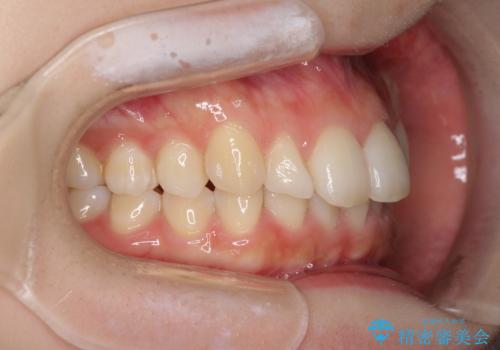

- 上の前歯が出っ張っている気がするとのことで来院された患者様です。

急いで治す必要性がないとのことで、自分のペースでのんびりと治療を行えるインビザラインにて矯正治療を行うこととしました。

半年もせずにインビザラインを全く使用することができなくなってしまったので、治療開始から1年ほどでワイヤー矯正へ変更することとなりました。